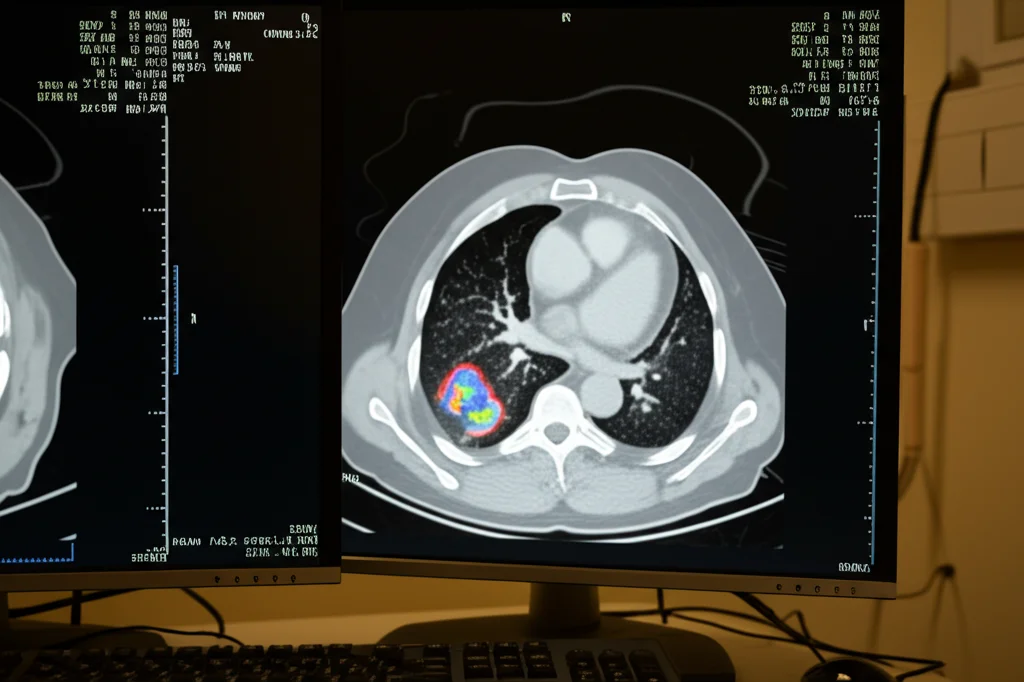

Lo studio suggerisce persino un possibile algoritmo diagnostico differenziato (mostrato nella Figura 4 del loro articolo) a seconda della presenza o assenza di neutropenia. E sottolinea anche il potenziale ruolo della PET-CT con 18F-FDG, una metodica di imaging funzionale che potrebbe aiutare a scovare lesioni “nascoste” e a stadiare meglio la malattia, specialmente nei casi dubbi o disseminati. Noi stessi, come gruppo di ricerca, stiamo studiando attivamente l’utilità della PET-CT nelle infezioni fungine e speriamo di avere presto dati più solidi da uno studio multicentrico in corso (NCT05688592).